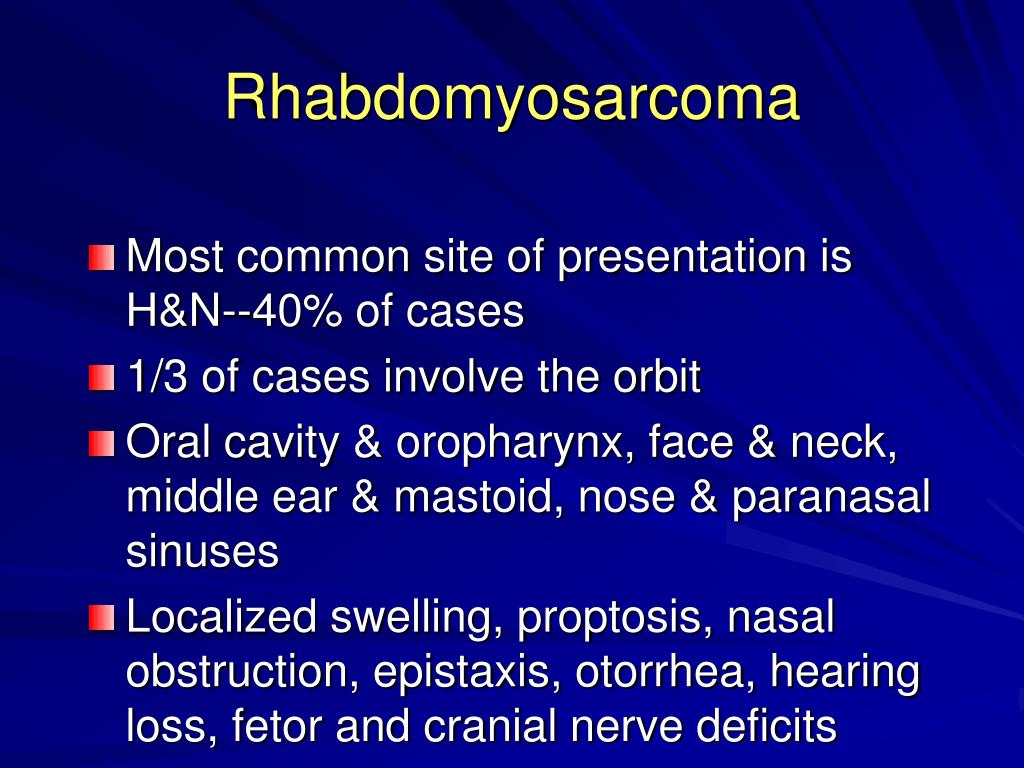

PPT - Pediatric Head And Neck Malignancies PowerPoint Presentation

www.slideserve.com

www.slideserve.com

presentation pediatric rhabdomyosarcoma neck head malignancies cases ppt powerpoint